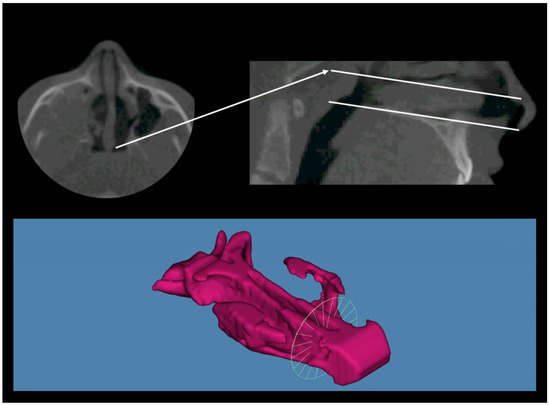

- Osorio, F.; Perilla, M.; Doyle, D.J.; Palomo, J.M. Cone beam computed tomography: An innovative tool for airway assessment. Anesth. Analg. 2008, 106, 1803–1807. [Google Scholar] [CrossRef]